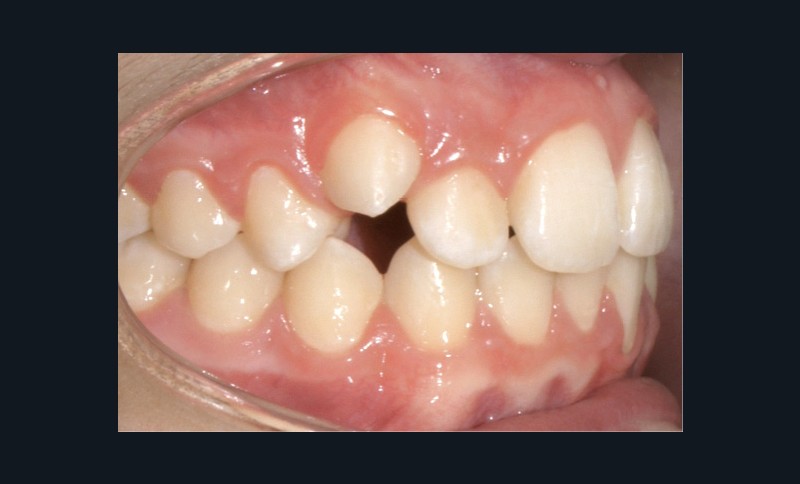

Examen endo-buccal (fig. 2a-e)

Au niveau des relations occlusales, on observe une Classe I molaire associée à une Classe II canine de 2 mm à droite ainsi qu’une Classe II molaire de 1 mm et une Classe II canine de 3 mm à gauche. Le surplomb est normal.